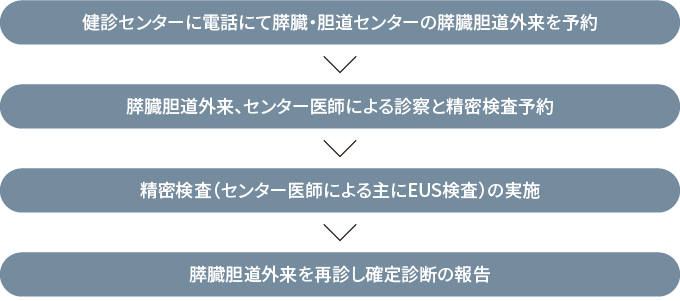

申し込みは下記にお電話いただくか、直接健診センターで受け付けております。

(申込み時に簡単な問診を行います)

電話:025-552-8835 健診センター 膵がん・胆道がんドック予約担当

(受付時間:午後1:00~午後4:00 *土日祝祭日を除く)

問診、採血、MRI、により膵がん、胆道がんの可能性のある方をスクリーニングします。

17,600円(税込)

(糸魚川市民の45歳以上の方には、糸魚川市より半額の補助が出ます。申し込み時にお申し出ください。)

膵臓・胆道に不安のある方で直接、センターへの受診を希望される場合は水曜日の午前以外でも外科一般外来で診察をおこなっております。

治療進行中は両センター間で治療方針に関しての情報交換が行われ続けます。